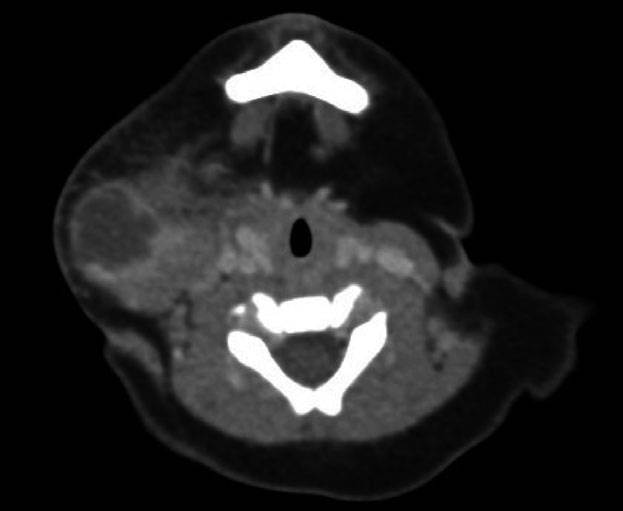

Figure 2 Computed image in the transverse plane of the airway at cricoid in a 3-month-old girl. Note that the elliptical shape is maintained although there is less difference between the anteroposterior and the transverse dimensions.

作者在两个水平(声门下和环状软骨环,图1和图2)测量喉部的横径和前后径。由2位作者分别对影像进行测量,并由第3名作者对测量结果进行验证。所有作者在测量时均不知道患儿的年龄。测量结果包括声门下和环状软骨水平气道的横径和前后径。椭圆形或圆形横截面的计算使用公式Area =π (½T × ½AP)。

不同性别或不同年龄(小于6月和大于6月)患者的测量结果没有差异。总体而言,从声门下水平到环状软骨水平其横径的大小是增加的(5.3 ± 0.84 mm vs 6.1 ± 0.86 mm),而前后径却是减少的(7.2 ± 0.87 mm vs 6.7 mm ± 0.75 mm),其差异均具有统计学意义。声门下横径和前后径的比值是0.74,而环状软骨处横径和前后径的比值是0.89。两个水平的横截面积相似,分别是声门下29.9 ± 7.5 mm2和环状软骨水平32.1 ± 7.8 mm2。声门下和环状软骨的测量结果显示前后径均大于横径,因此气道在这两个水平均呈椭圆形(表1)。